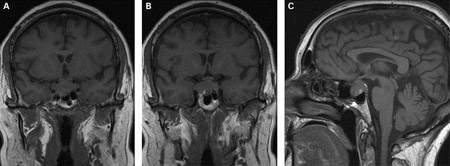

If prolactin levels are significantly elevated, cranial MRI is indicated to rule out pituitary adenoma.[1][31][Figure caption and citation for the preceding image starts]: (A) Coronal T1-weighted MRI scan showing a pituitary mass with expansion of the pituitary fossa (B) Coronal T1-weighted MRI scan showing a pituitary mass extending into the cavernous sinus, particularly on the right (C) Sagittal T1-weighted MRI scan of the pituitary tumourBMJ Case Reports 2009; doi:10.1136/bcr.08.2009.2193 [Citation ends].